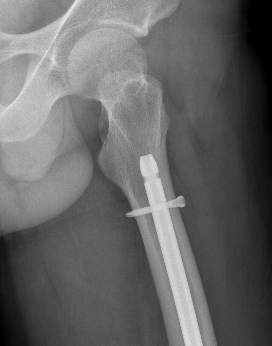

AO Type A: Supracondylar / Extra-condylar

Xray

Retrograde IM nail

Retrograde Nail

Surgical Technique

- ensure AP of hip for proximal locking screw